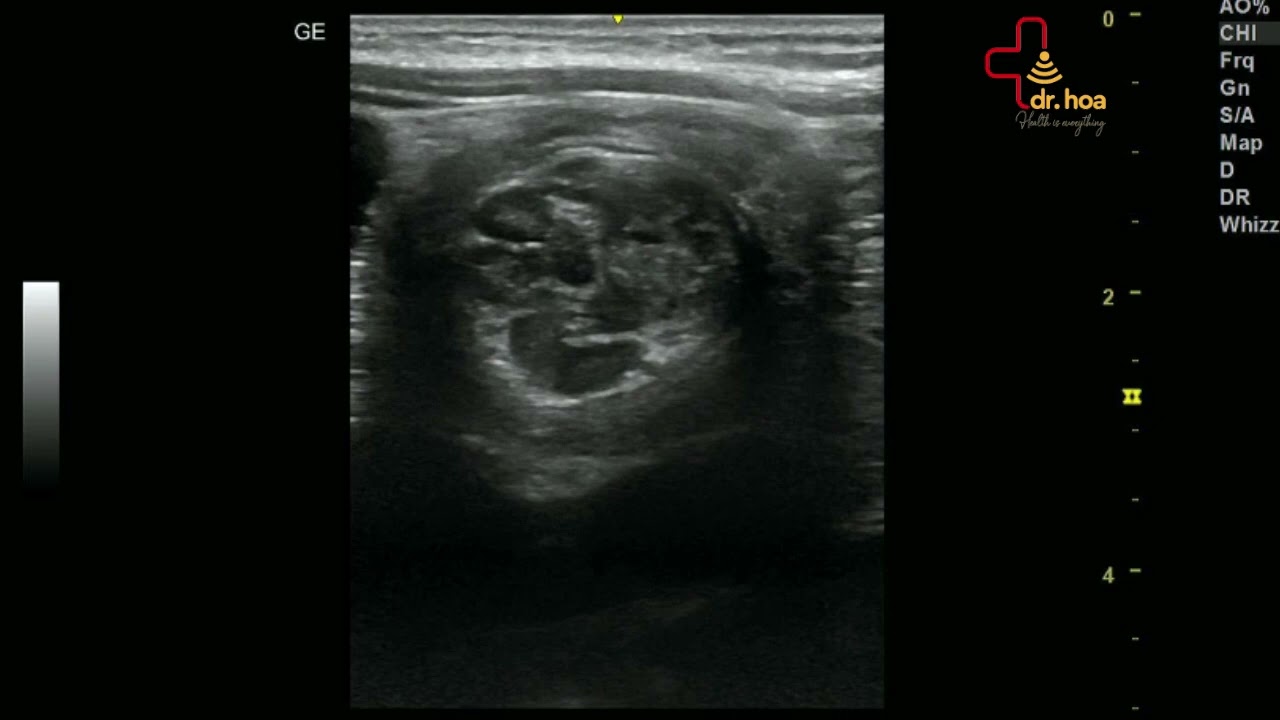

Hình ảnh siêu âm bụng phát hiện lồng ruột.Phương pháp siêu âm này giúp bác sĩ khảo sát nhiều cơ quan quan trọng trong ổ bụng như: